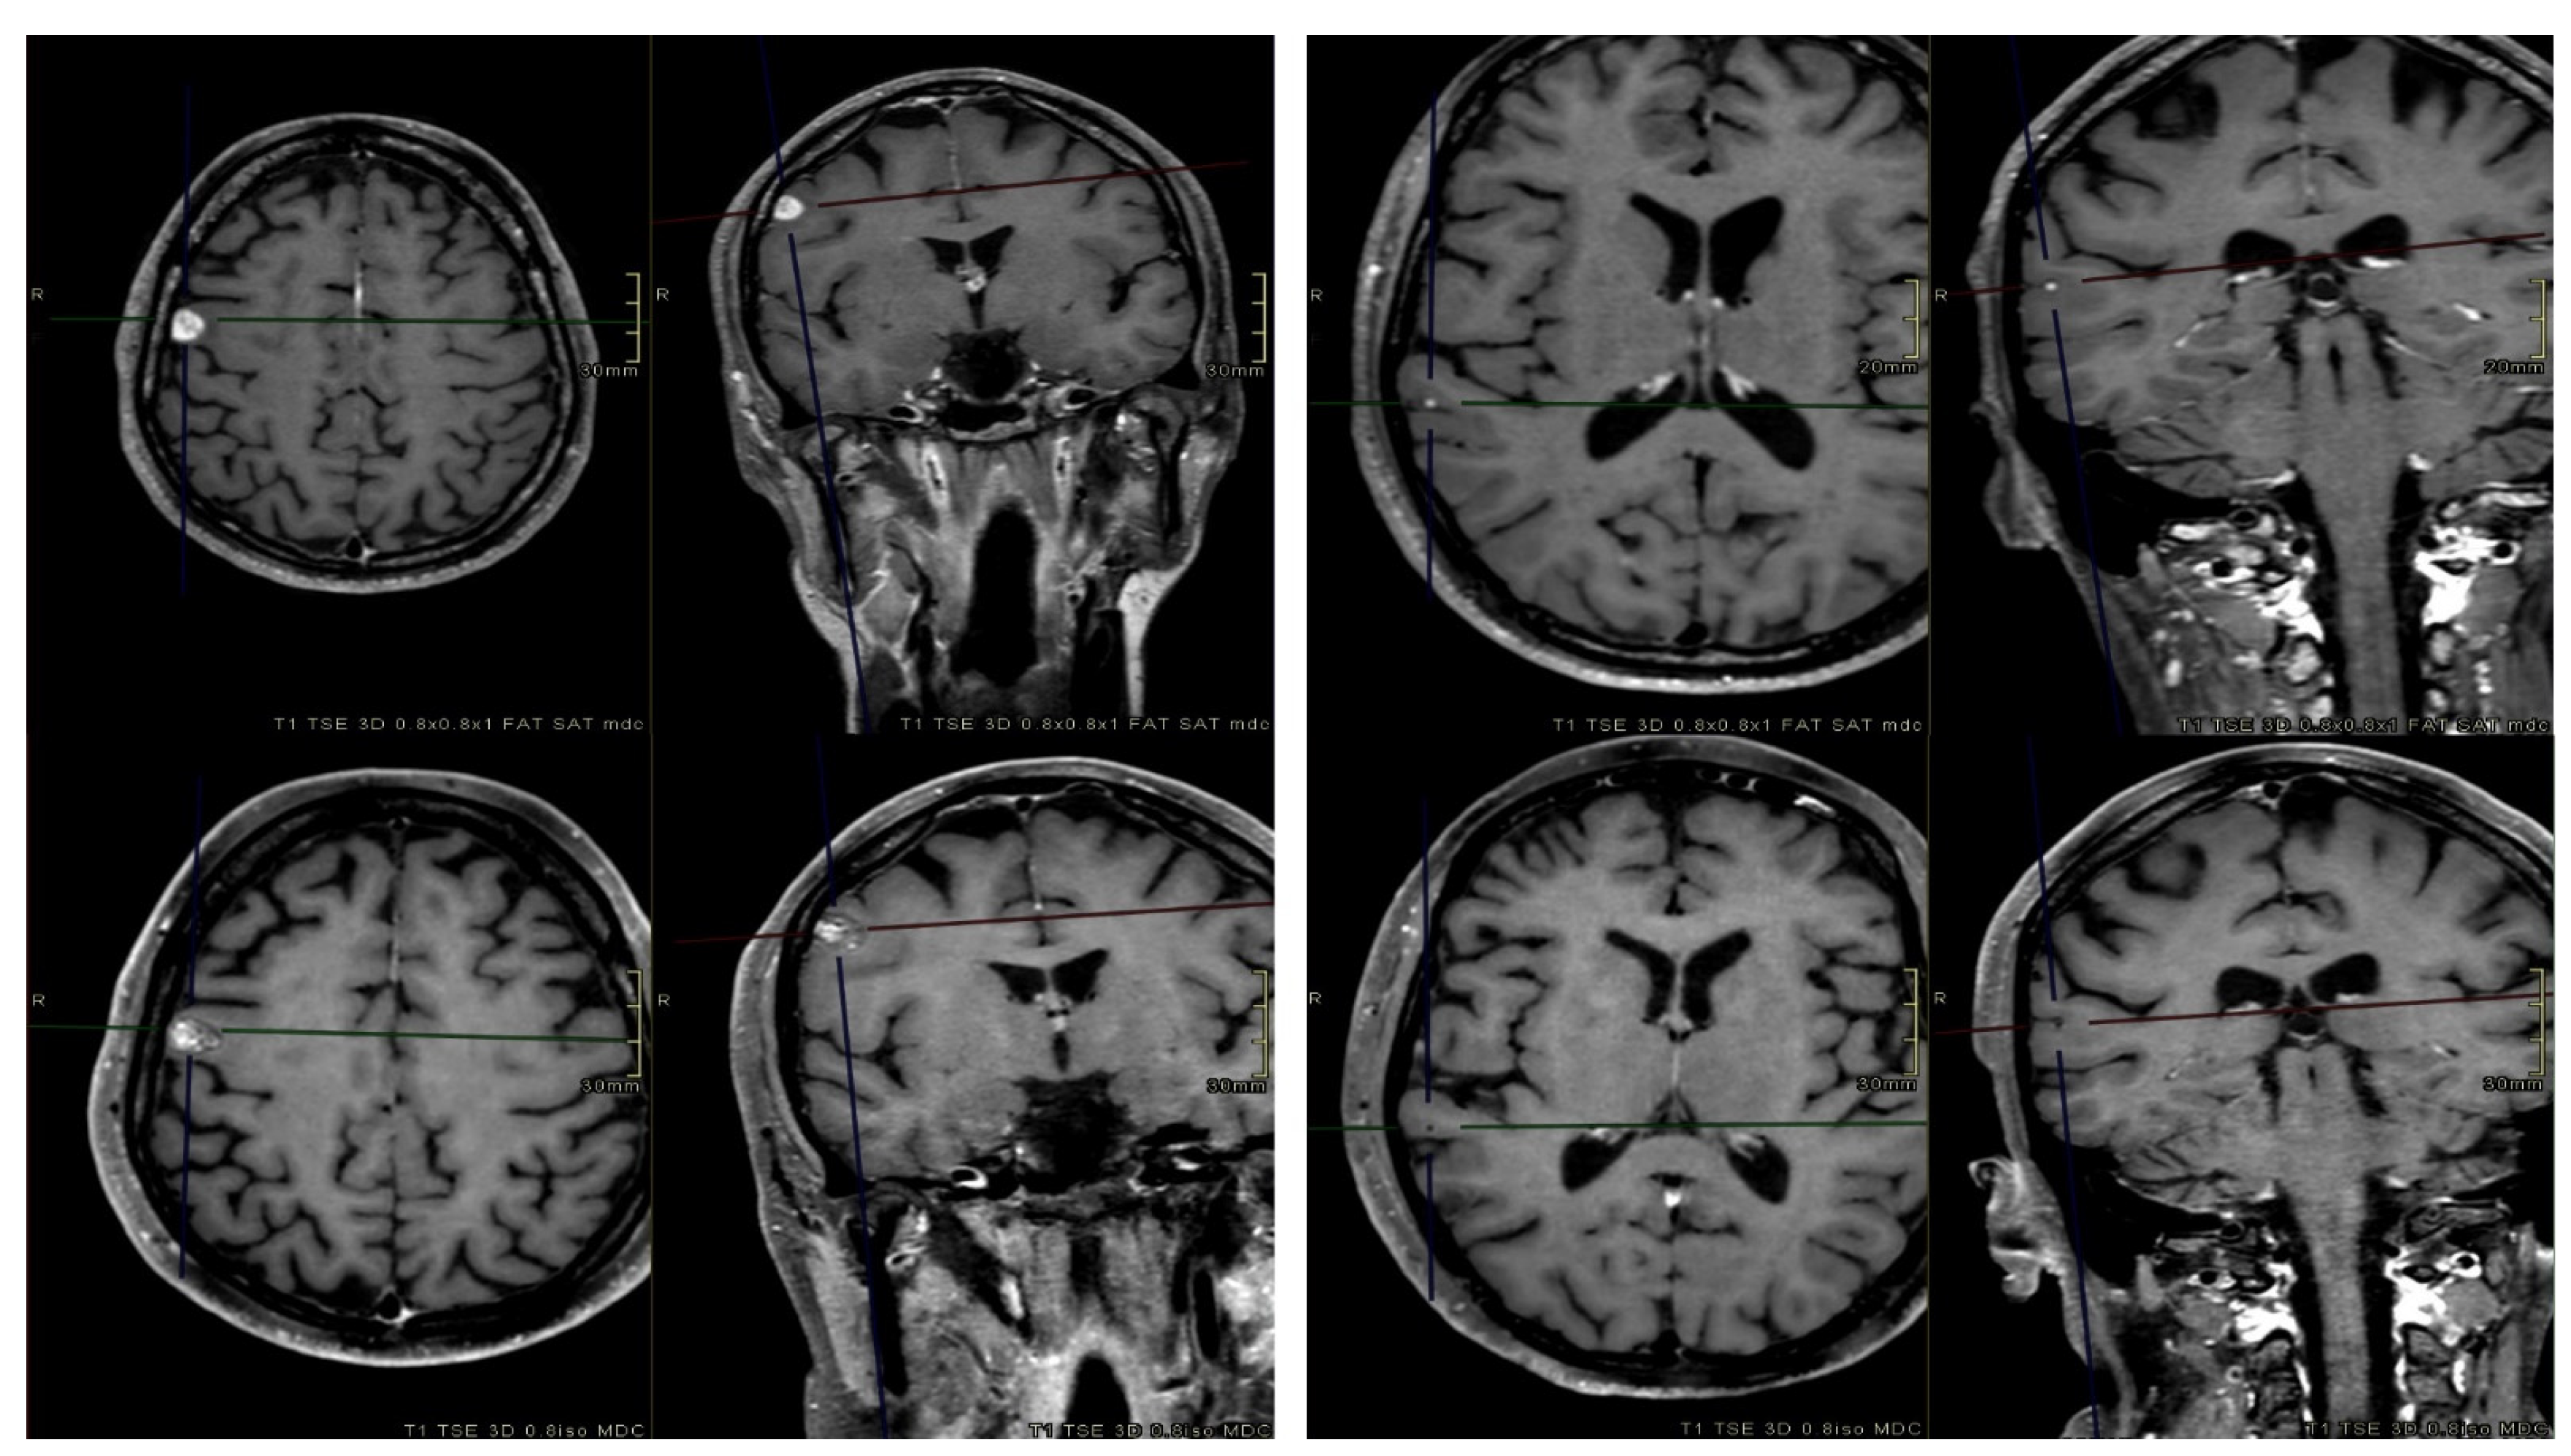

The intrafractional rotations and translations were applied to the planning CT (Fx-CT) using the MIM software, version 7.1.4 (MIM Software Inc., Cleveland, OH, USA). Fx-CT was rigidly co-registered with the planning CT to transfer the original patient RT structures. The accuracy of the registration was qualitatively analyzed by using anatomical landmarks as reference points. Redundantly, an expert radiation oncologist validated the transferred structures by comparing them with the planning MRI. The resulting 3D GTV barycenter shift was calculated by taking the difference between the barycenter of each lesion in the original and Fx-CT images. The original patient-specific treatment plan was recalculated on the corresponding Fx-CT with Monaco Monte Carlo TPS, using the same algorithm and calculation properties. For fSRS treatments, the three different recalculated plans from each fraction were summed on the simulation CT to estimate the total cumulative plan. Thus, plans involving translations and rotations (Fx-plans) allowed the simulation of doses that were actually delivered to the patients. Figure 2 illustrates the dose recalculation workflow in a schematic representation.

Figure 2. Schematic representation of the dose recalculation workflow.

Figure 3. Axial and coronal contrast-enhanced T1-weighted pre-treatment (top) and post-treatment (bottom) MRI sequences of two BM. At the first MRI FUP (3 months after radiotherapy), one BM (right) was in progression, while the other one (left) completely regressed.